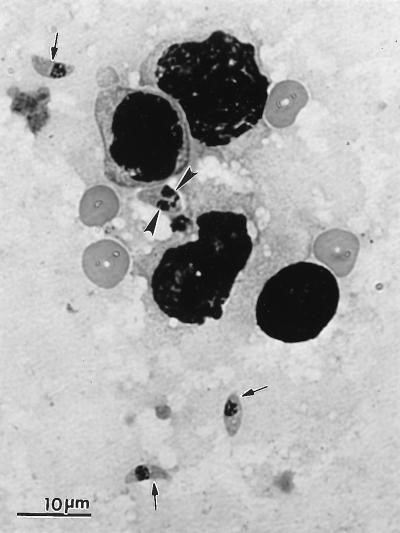

Hình 1.Thể hoạt động (tachyzoit) của T. gondii. Một tachyzoite đang phân chia (tam giác) và các tachyzoit đơn (mũi tên).

Phết tế bào phổi mèo, nhuộm bằng thuốc nhuộm Giemsa.[3]